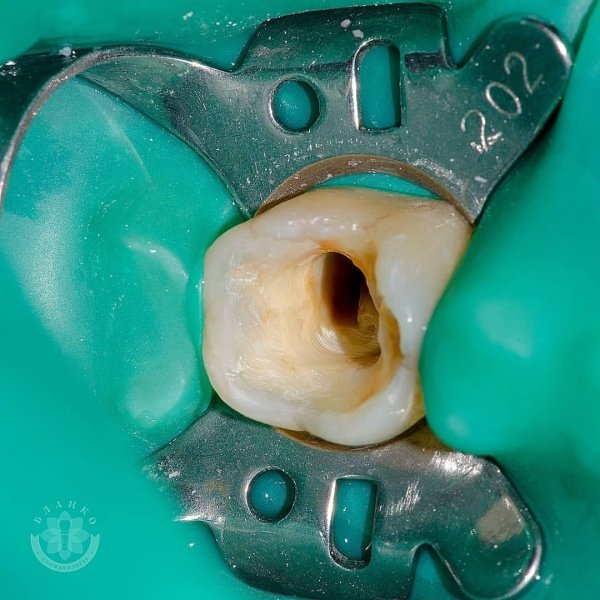

Глибока руйнація😳👿

Чим глибше під ясна зруйнований зуб — тим складніше він піддається адекватному відновленню☝

У даному клінічному випадку два зуби відновлено культевими вкладками, виготовлено коронки з оксиду цирконію, третій зуб відновлено за допомогою прямої фотополімерної реставрації 😁👍